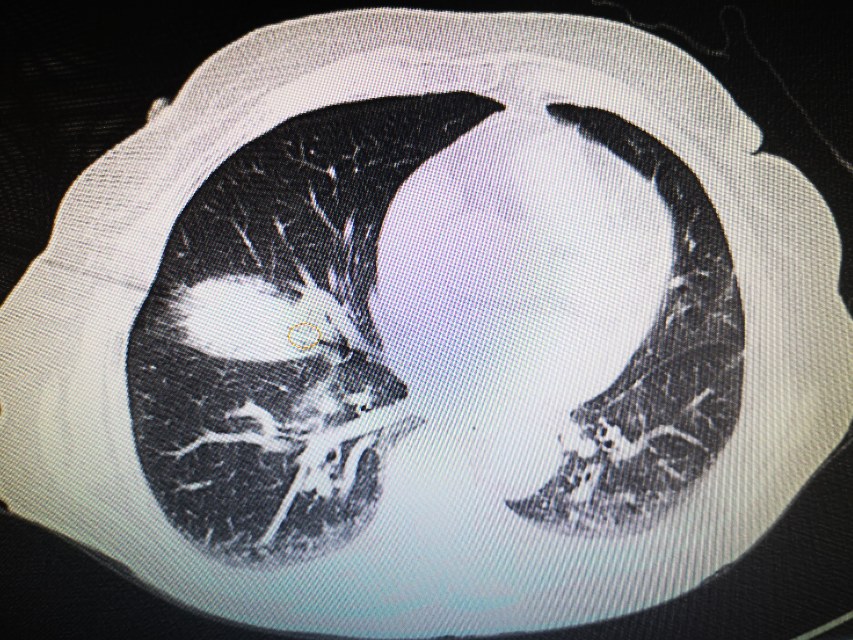

接过CT片,李医生仔细分析起来。果然又是一例顽皮的肺磨玻璃。只见,在右肺中叶外侧段,一个8mm的混合磨玻璃结节,躲藏在封闭的房间内,也就是我们常常说的密室。密室的外墙是右肺中叶肺动脉、中叶支气管、斜裂胸膜,门是中叶分支动脉。通往密室的是斜裂和右肺中叶动脉和支气管形成的一个小通道。好在还有路径可以通过!老话说谨言慎行,一点没错😂,不过谁让咱是江湖兵器排行前十的小李飞针呢,为了最小的创伤解决患友的疾苦,咱们必须不畏艰难,知难而进,迎难而上!将密室中的磨玻璃结节消灭!

在穿刺针进入皮肤的那一刻,李医生就有感觉,今天的针应该是很准的。为了避开血管和胸膜,李医生中途停下两次,调整消融针的方向和角度,确保不损伤任何一根微小的血管,确保不影响任何一寸薄弱的胸膜!这个过程比穿的准要和更难更复杂!在团队的集体努力下,小李飞针终于避开所有血管、支气管和胸膜,到达了肺结节的中心!李医生的几位助手都长舒一口气。此时,我们回头看看钟奶奶,发现她安静的闭着眼睛,好像睡着了。就是现在,开始消融,经过仔细调整消融参数后,手术顺利取得了预期的效果。也没有气胸咯血等并发症。密室消磨,完美成功!